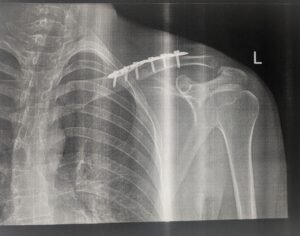

Моя мама потрапила до нього зі складним випадком — перелом в області плеча. Ситуація вимагала високої точності, досвіду та швидких рішень. Операція пройшла швидко та успішно.